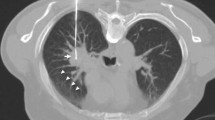

All RFA procedures (Fig. 1) were approved by a multidisciplinary board, attended by oncologists, radiation therapists, radiologists, thoracic surgeons, a pathologist and an interventional radiologist. RFA was preferred according to patient general status, number and location of tumours, or because of patient’s choice. All patients underwent a thoracic CT scan examination immediately before treatment in order to confirm the number and size of tumours. All procedures were done under general anaesthesia and CT guidance. The RFA protocol was the same as that described in previous studies [6]. Briefly, an expandable electrode made from 10 tines (LeVeen CoAccess; Boston Scientific, Natic, Massachusetts, US) with a 15-gauge coaxial system was used. RFA electrodes were 15 cm long with a 3-, 3.5- or 4-cm array diameter when expanded according to the targeted tumour diameter. Patients were placed in the prone, supine or lateral positions, whichever provided access to the best puncture pathway. The needle placement was performed under sequential scans (SmartStep, GE Medical Systems, Milwaukee, Wisconsin, US). Then multiplanar reconstructions from a helical CT volume were obtained after deployment of the electrodes in order to assess correct positioning.

Right upper lobe metastasis (22 mm) in a 60-year-old woman with breast cancer. a Pretreatment CT scan in an axial plane. b Puncture and needle placement. c RFA probe placement in the middle of the lesion. d Post-RFA biopsy, using the same coaxial system (without any additional puncture). e Control acquisition after RFA and post-RFA biopsy showing an ablation zone covering the initial lesion

A post-RFA biopsy of one tumour in each patient was obtained through the coaxial cannula left in place after retrieval of the RF probe. A 18-gauge semiautomatic core needle (Quick-core, Cook, Bloomington, Indiana, US) was used to obtain a sample for pathological analysis. After retrieval of the coaxial cannula, pneumothoraces were aspirated, if present, and a chest tube was inserted if the pneumothorax recurred after aspiration.